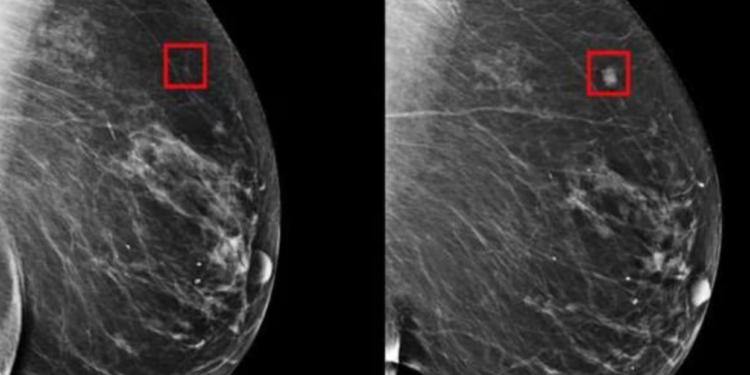

El sistema de IA utiliza un modelo de aprendizaje profundo, entrenado con miles de imágenes mamográficas para identificar patrones tempranos que indican la presencia de células cancerosas.

De acuerdo con los investigadores del MIT, el sistema es capaz de detectar el cáncer hasta cuatro o cinco años antes de que se vuelva visible en una mamografía estándar.

El estudio del MIT ha sido publicado en la revista científica ‘Radiology’. Los investigadores del MIT utilizaron imágenes mamográficas de más de 60.000 pacientes para entrenar el sistema de IA.

El sistema fue entonces evaluado en un grupo separado de pacientes y se encontró que era capaz de detectar el cáncer de mama con una precisión del 94,5 %.